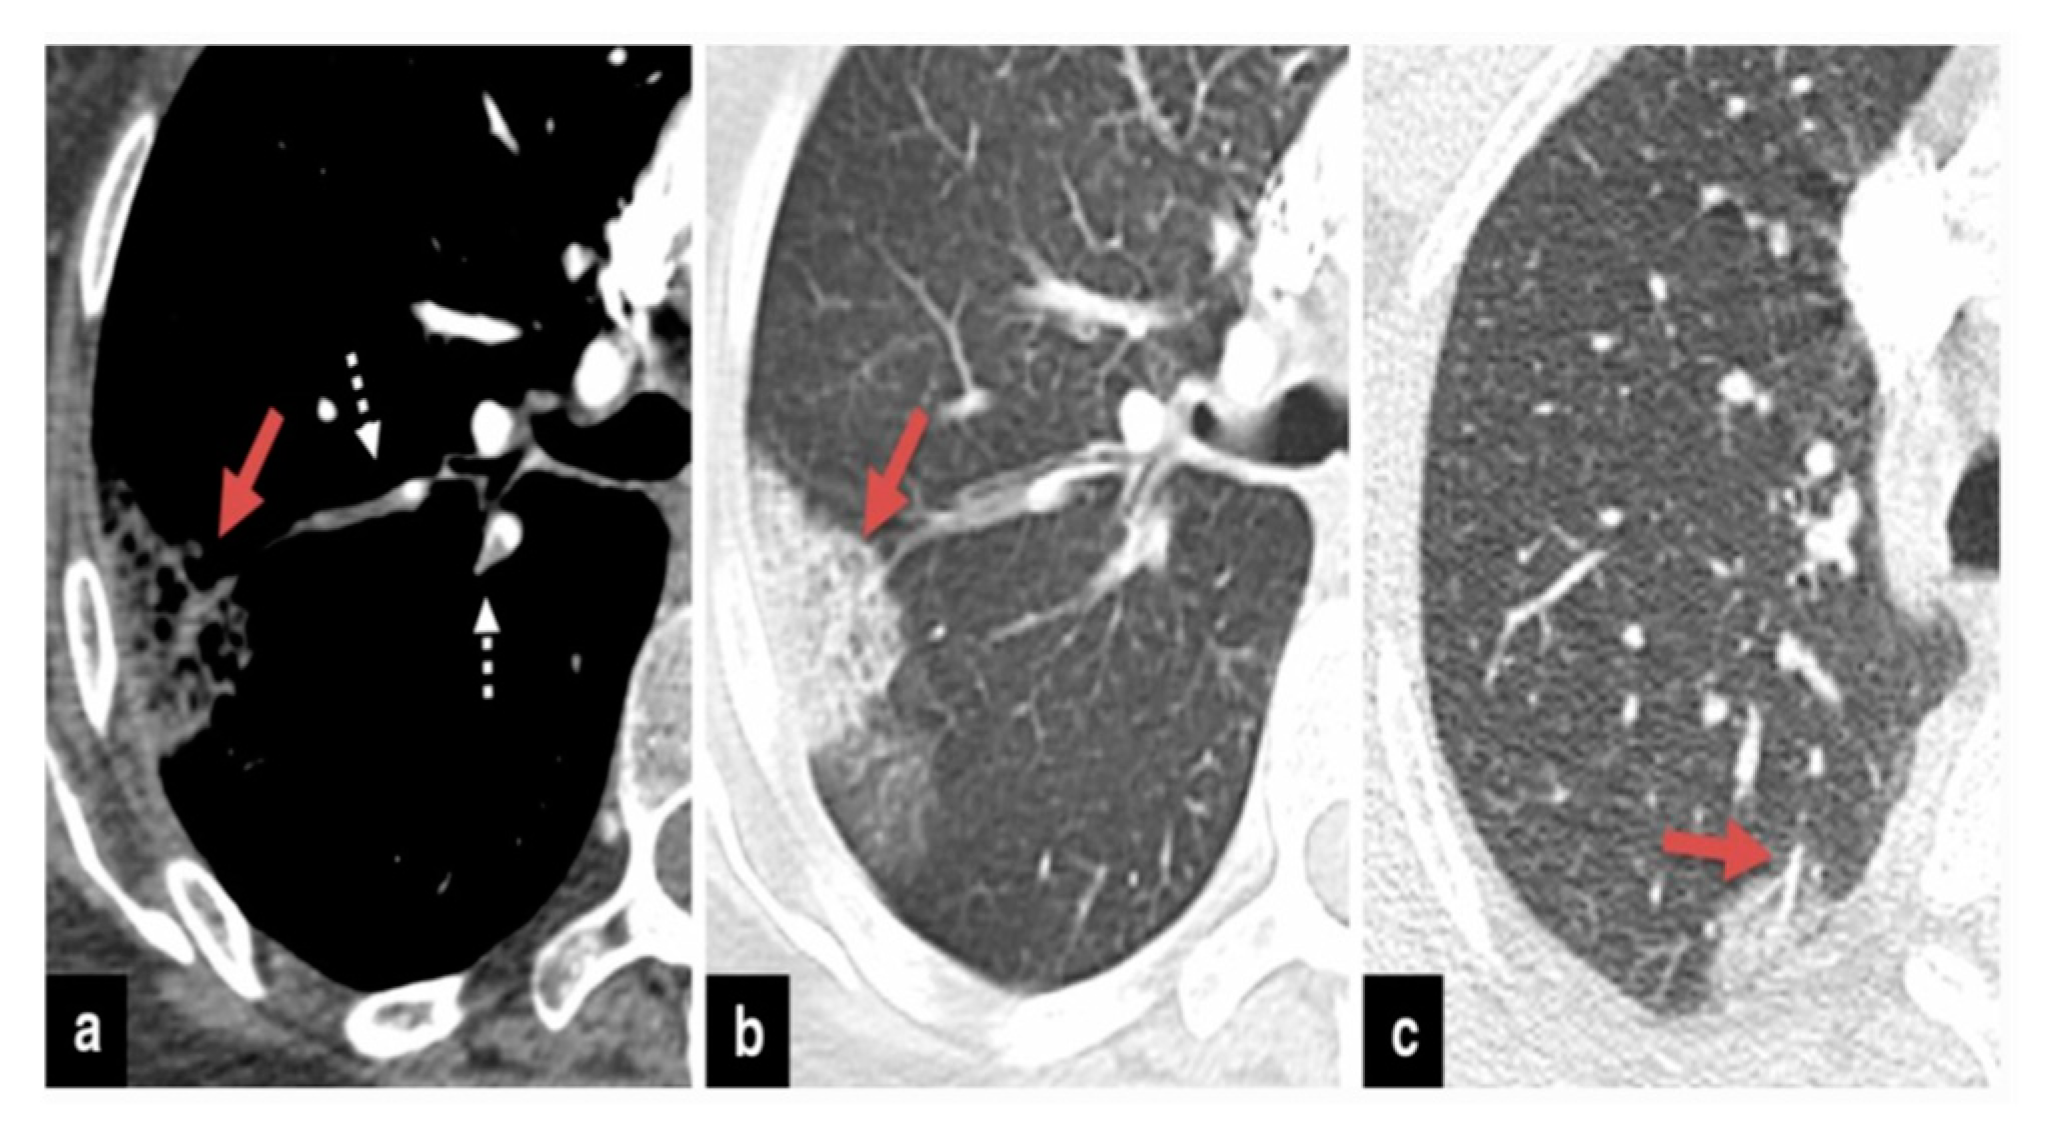

The precise contribution of pulmonary embolism (PE) to mortality in patients with SARS-CoV-2 remains uncertain due to the fact that not all patients routinely undergo CT pulmonary angiography and because there’s a limited number of autopsy studies available . However, in cases of patients suspected of having SARS-CoV-2 and exhibiting a strong clinical suspicion for PE, which can be determined based on symptoms like hemoptysis, unexplained rapid heart rate, or signs and symptoms of deep venous thrombosis alongside acute deterioration upon patient mobilization, it is advisable to consider performing CT pulmonary angiography (

Figure 1) .

Figure 2,

Figure 3 and

Figure 4) .